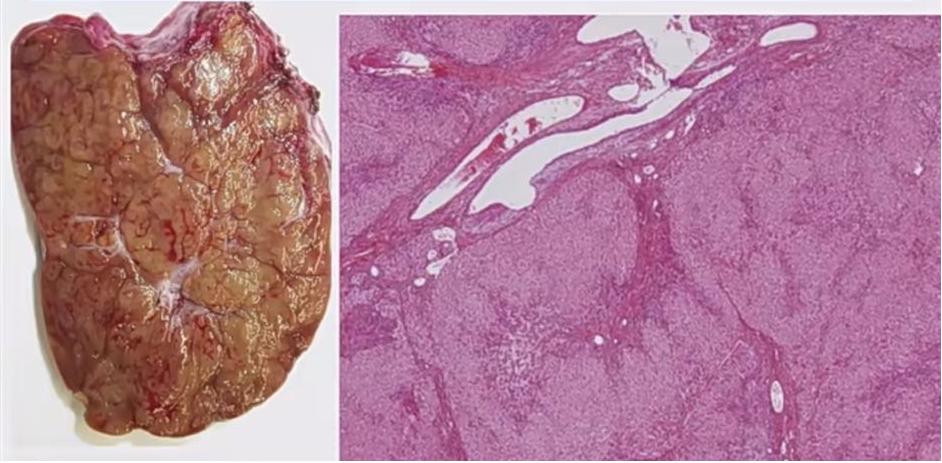

FNH大体形态和镜下表现,镜下可见占位中央区变形的血管(图1-3)。

图1

图2

图3